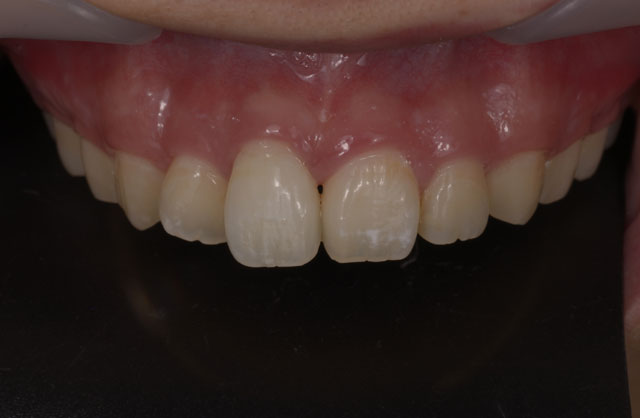

治療前のシミュレーション

施術前のレントゲン

― 治療後 ―

計画した位置に正確に施術することで良好な審美結果が得られます

コンピューターガイデッドインプラント治療 + 歯科用顕微鏡を用いたマイクロサージェリー 審美的に良好な結果が得られています

当院では、コンピューターガイデッド インプラント治療で正確な位置にインプラント手術を行い、そして前歯などの審美領域では顕微鏡を使用したマイクロサージェリー(顕微鏡下手術)を行うことで傷跡の目立ちにくい自然な仕上がりのインプラント治療を行っています。